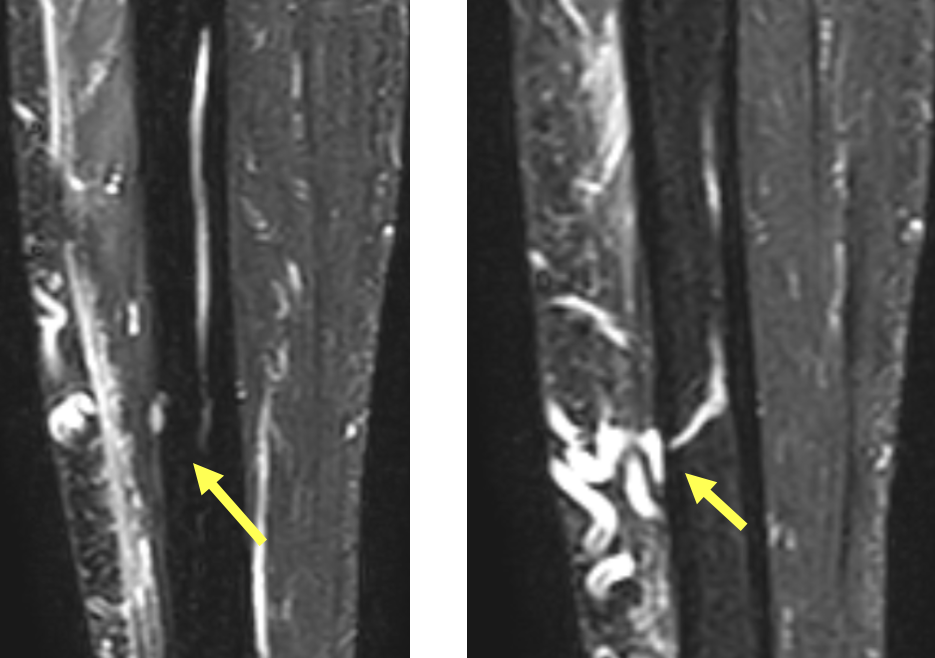

- Ausgeprägte Tenosynovitiden, v.a. der Flexorensehnen (Pfeile) (T1 FS KM)

- Synovitis der MCP D5, PIP und DIP Gelenke D5 (Pfeile) (T1 FS KM)

- Diffuses Weichteilödem entlang des 5. Strahles mit korrespondierender KM- Aufnahme (Pfeile) (T1 FS KM)